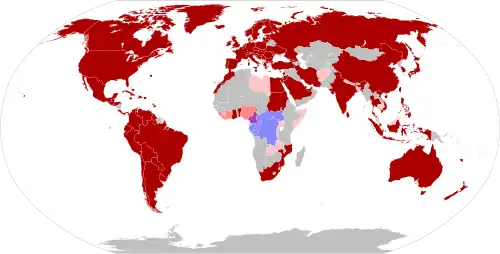

Mpox is endemic in Central and Western Africa, where several species of mammals are suspected to act as a natural reservoir of the virus.[1] The first human cases were diagnosed in 1970 in Basankusu, Democratic Republic of the Congo.[12] Since then, the frequency and severity of outbreaks have significantly increased, possibly as a result of waning immunity since the cessation of routine smallpox vaccination.[12] A global outbreak of clade II in 2022–2023 marked the first incidence of widespread community transmission outside of Africa. In July 2022, the World Health Organization (WHO) declared the outbreak a public health emergency of international concern (PHEIC). The WHO reverted this status in May 2023,[13] as the outbreak came under control, citing a combination of vaccination and public health information as successful control measures.[14]

An outbreak of new variant of clade I mpox (known as clade Ib) was detected in the Democratic Republic of the Congo during 2023.[15] As of August 2024, it had spread to several African countries, raising concerns that it may have adapted to more sustained human transmission.[16][17] In August 2024, the WHO declared the outbreak a public health emergency of international concern.[18][13]

Following the 2022–2023 outbreak, mpox (clade IIb) remains present in the human population outside Africa at very low levels.[81] In November 2023, the WHO reported increasing numbers of cases of mpox (clade I) in the Democratic Republic of the Congo, with 12,569 cases year-to-date and 651 fatalities; there was also the first evidence of sexual transmission of clade I.[82]

There has been a rise in mpoxvirus clade I infections in the Democratic Republic of the Congo (DRC) since November 2023, with more cases now reported in other African countries that previously had no mpox cases. Two imported cases were also found in Sweden and Thailand. As of August 23, 2024, over 20,000 mpox cases have been reported in 13 African Union Member States, with 3,311 confirmed cases and 582 deaths. Most cases are found in the DRC, where subclade Ia and Ib are prevalent.[83]

Clade Ib was linked to a reported mpox case in Sweden on August 15, 2024, which was related to traveling to an African country where the virus is found. Despite the low incidence, cases associated with clade II have been reported in EU/EEA countries since. In 2024, the WHO added the monkeypox virus to its list of "priority pathogens" that could cause a pandemic.[84]

An outbreak of mpox caused by clade IIb of the virus was first identified in May 2022.[111] The first case was detected in London, United Kingdom, on 6 May, in a patient with a recent travel history from Nigeria, where the disease is endemic.[112][113] Subsequent cases were reported in an increasing number of countries and regions.[120] In July 2022, the WHO declared the outbreak a public health emergency of international concern. This status was terminated in May 2023 due to steady progress in controlling the spread of the disease, attributed to a combination of vaccination and public health information.[121] As of August 2024, clade IIb mpox cases outside of endemic regions in Africa continued to be reported at a low level.[91]

2023–2024 Central Africa outbreak

During 2023, a clade I outbreak of mpox disease in the Democratic Republic of the Congo resulted in 14,626 suspected cases being reported, with 654 associated deaths, making for a case-fatality rate of 4.5%. The outbreak continued into 2024, with 3,576 suspected mpox cases and 265 deaths reported in the Democratic Republic of the Congo through the first nine weeks of the year, making for an estimated CFR of 7.4%.[122]

Transmission of the virus in the outbreak appears to be primarily through sexual and close familial contact, with cases occurring in areas without a history of mpox, such as South Kivu and Kinshasa. An estimated 64% of the cases and 85% of fatalities have occurred in children. The outbreak consists of two separate sub-variants of clade I, with one of the sub-variants having a novel mutation, making detection with standard assays unreliable.[122][123]

The outbreak spread to the neighbouring country of the Republic of the Congo, with 43 cases reported in March 2024.[122] By August 2024, the outbreak spread further into central and southern Africa with cases of clade I and clade II strains reported in Burundi, Rwanda, Uganda, Kenya, Côte d'Ivoire, and South Africa.[92][17]

The WHO declared a global health emergency in August 2024.[18][13][124] Sweden became the first non-African country to report a case of clade I mpox.[125] A case of mpox was confirmed in Pakistan.[126]